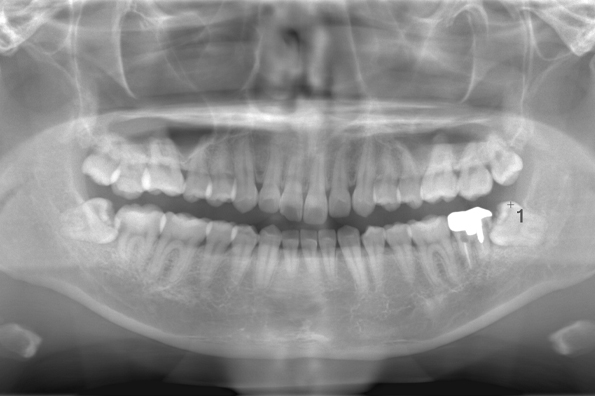

CASE 11

| 年齢・性別 | 33歳・男性 |

| 主訴 | 左上下親知らず抜きたい |

| 抜歯期間 | 30分 |

| 抜歯費用 | 約2,500円(保険内) 別途CT撮影で3,000円 (2022年7月現在) |

| 抜歯内容 | 左上下の親知らず抜歯 |

| 治療方針 |

初めに右下の奥歯が痛いとのことでご来院されました。 右下の親知らずと7番目の歯がカリエスになっていたため、まずは右下の親知らず抜歯と7番目の感染根管治療を行いました。左上下の親知らずもカリエスになっているため、今回抜歯を行いました。 |